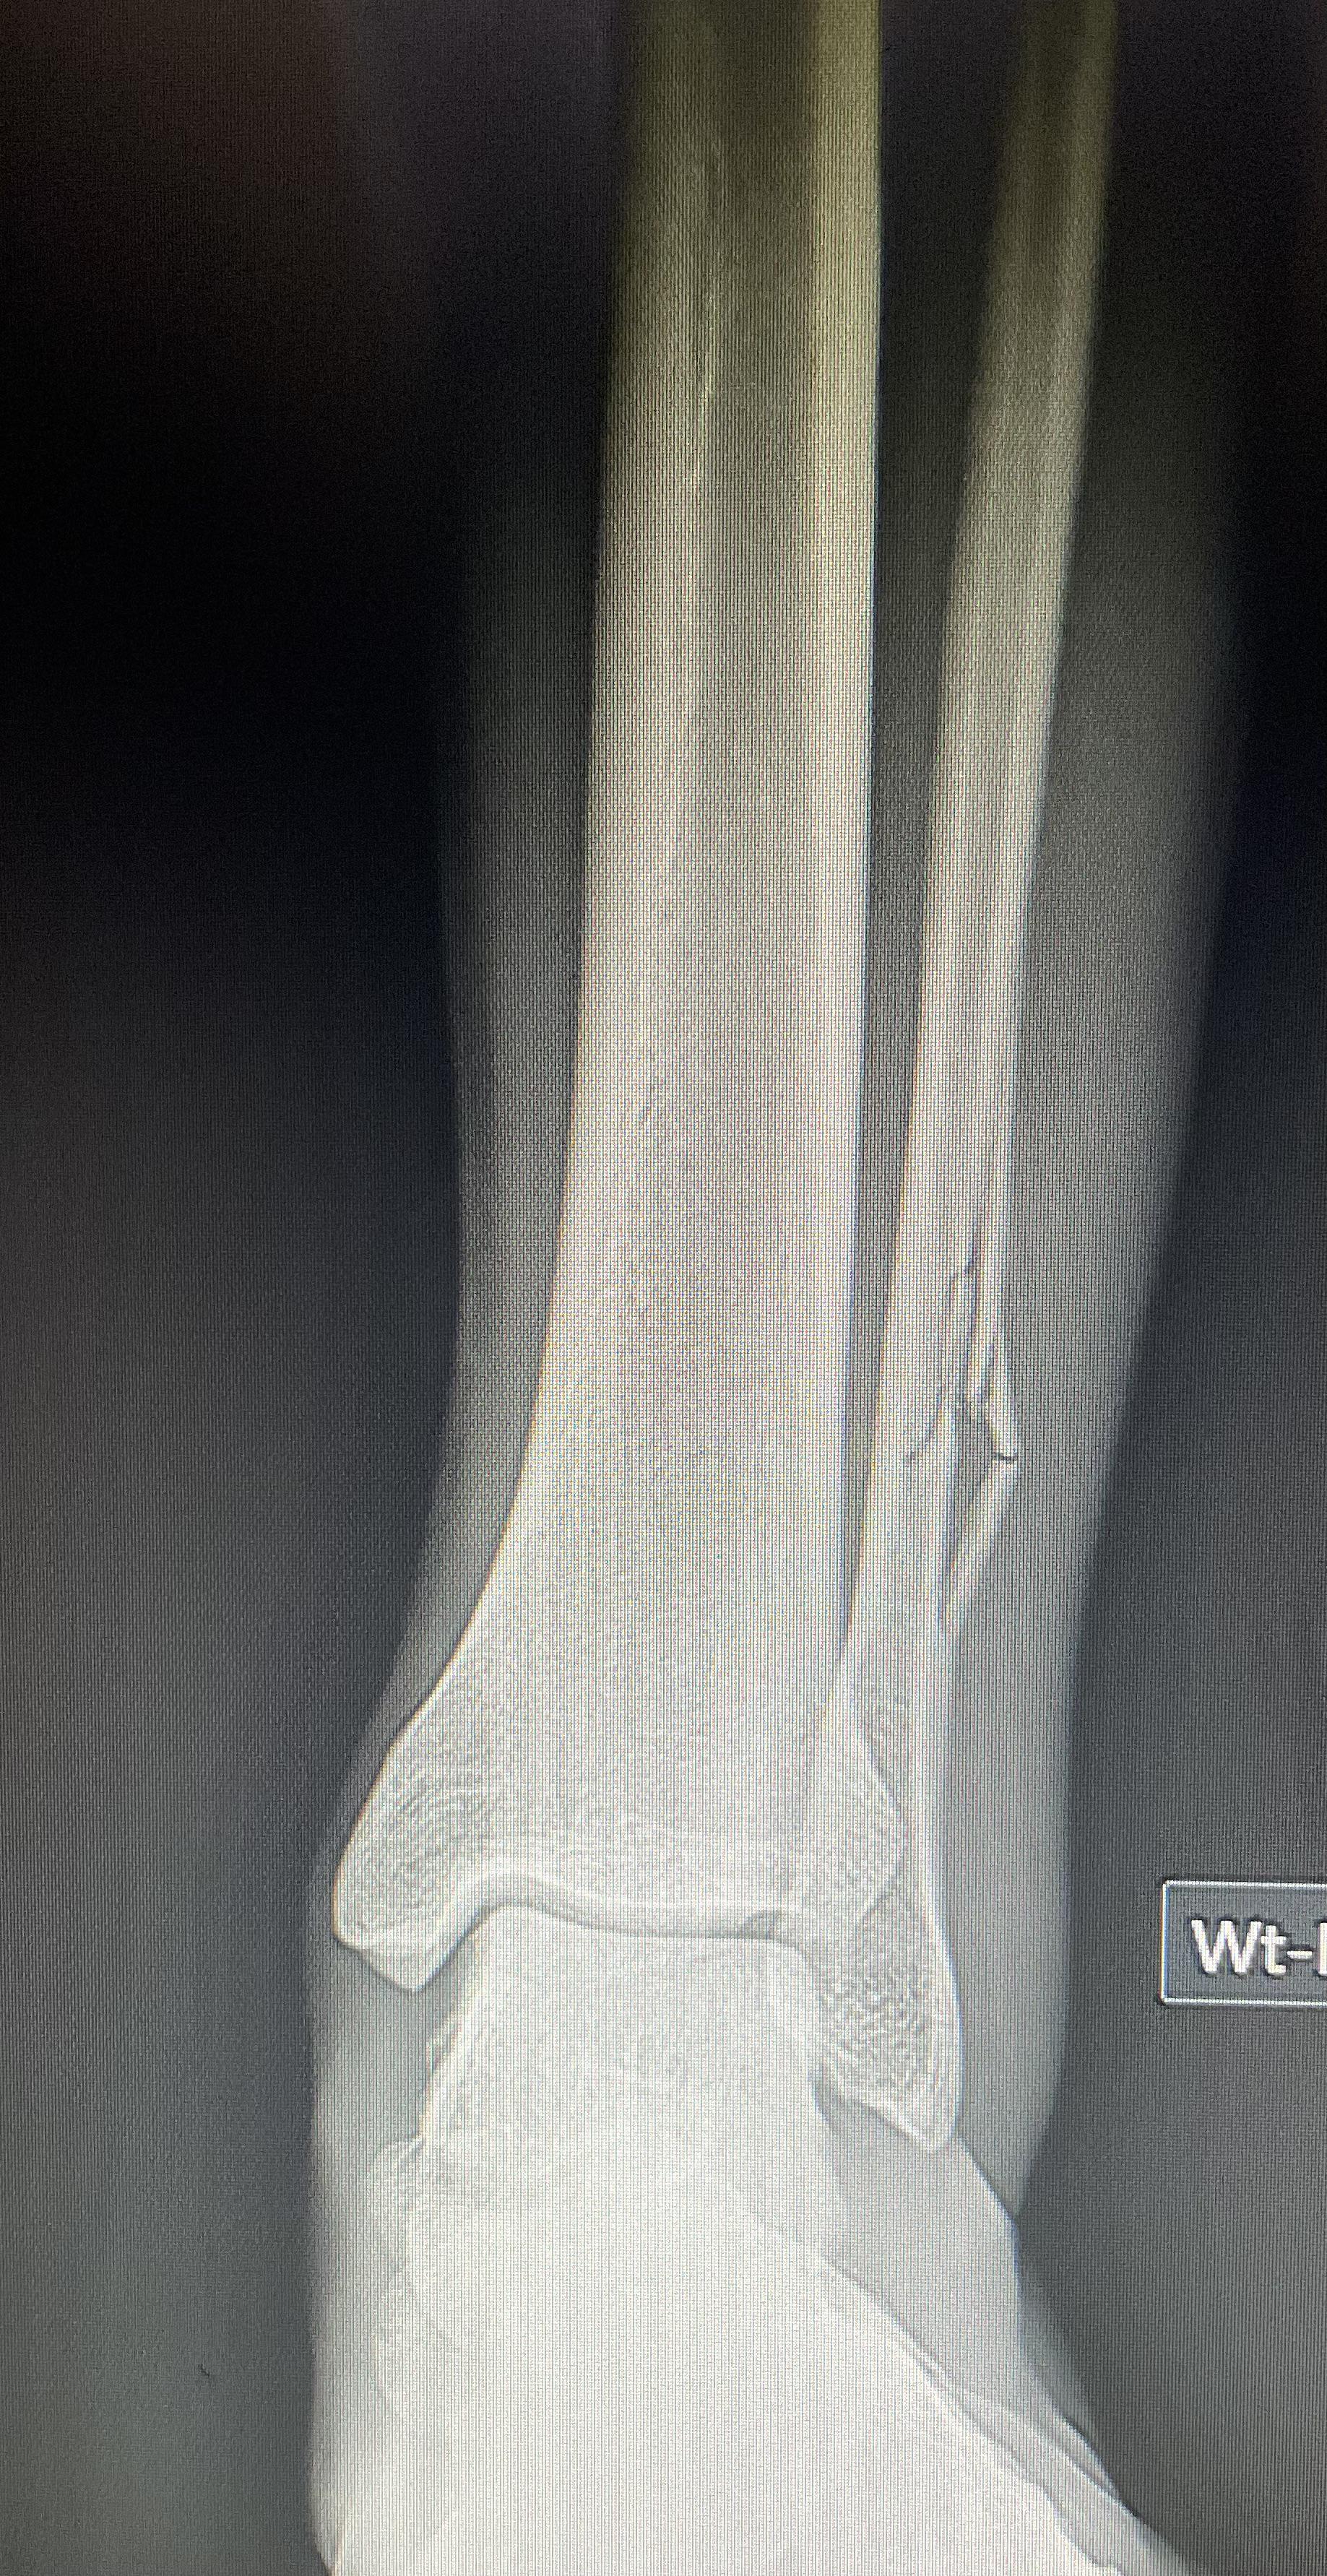

From nyboneandjoint.com

Soccer Injuries Shinbone Fractures New York Bone & Joint Specialists Stress Fracture From Soccer Stress fractures are small cracks or breaks in the bone caused by repetitive stress. In soccer players the most common stress fractures are found in: Three different types of fractures related to soccer are classified as acute types, stress fractures and avulsion. Second and fifth metatarsals and femur (older soccer players). Common stress fracture sites in football include the metatarsals,. Stress Fracture From Soccer.

From www.reddit.com

Interesting Fibula fracture in a soccer player r/Radiology Stress Fracture From Soccer In soccer players the most common stress fractures are found in: Second and fifth metatarsals and femur (older soccer players). Stress fractures are small cracks or breaks in the bone caused by repetitive stress. There is an increasing role for primary. In injury surveys of european. The optimal treatment method is determined by fracture location and configuration. Common stress fracture. Stress Fracture From Soccer.